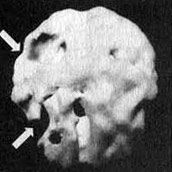

Мозг Эллен - последствия инсульта

Трехмерное изображение поверхности мозга, вид слева. Обратите внимание на обширную "дыру", сформировавшуюся в результате инсульта в левой лобной доле